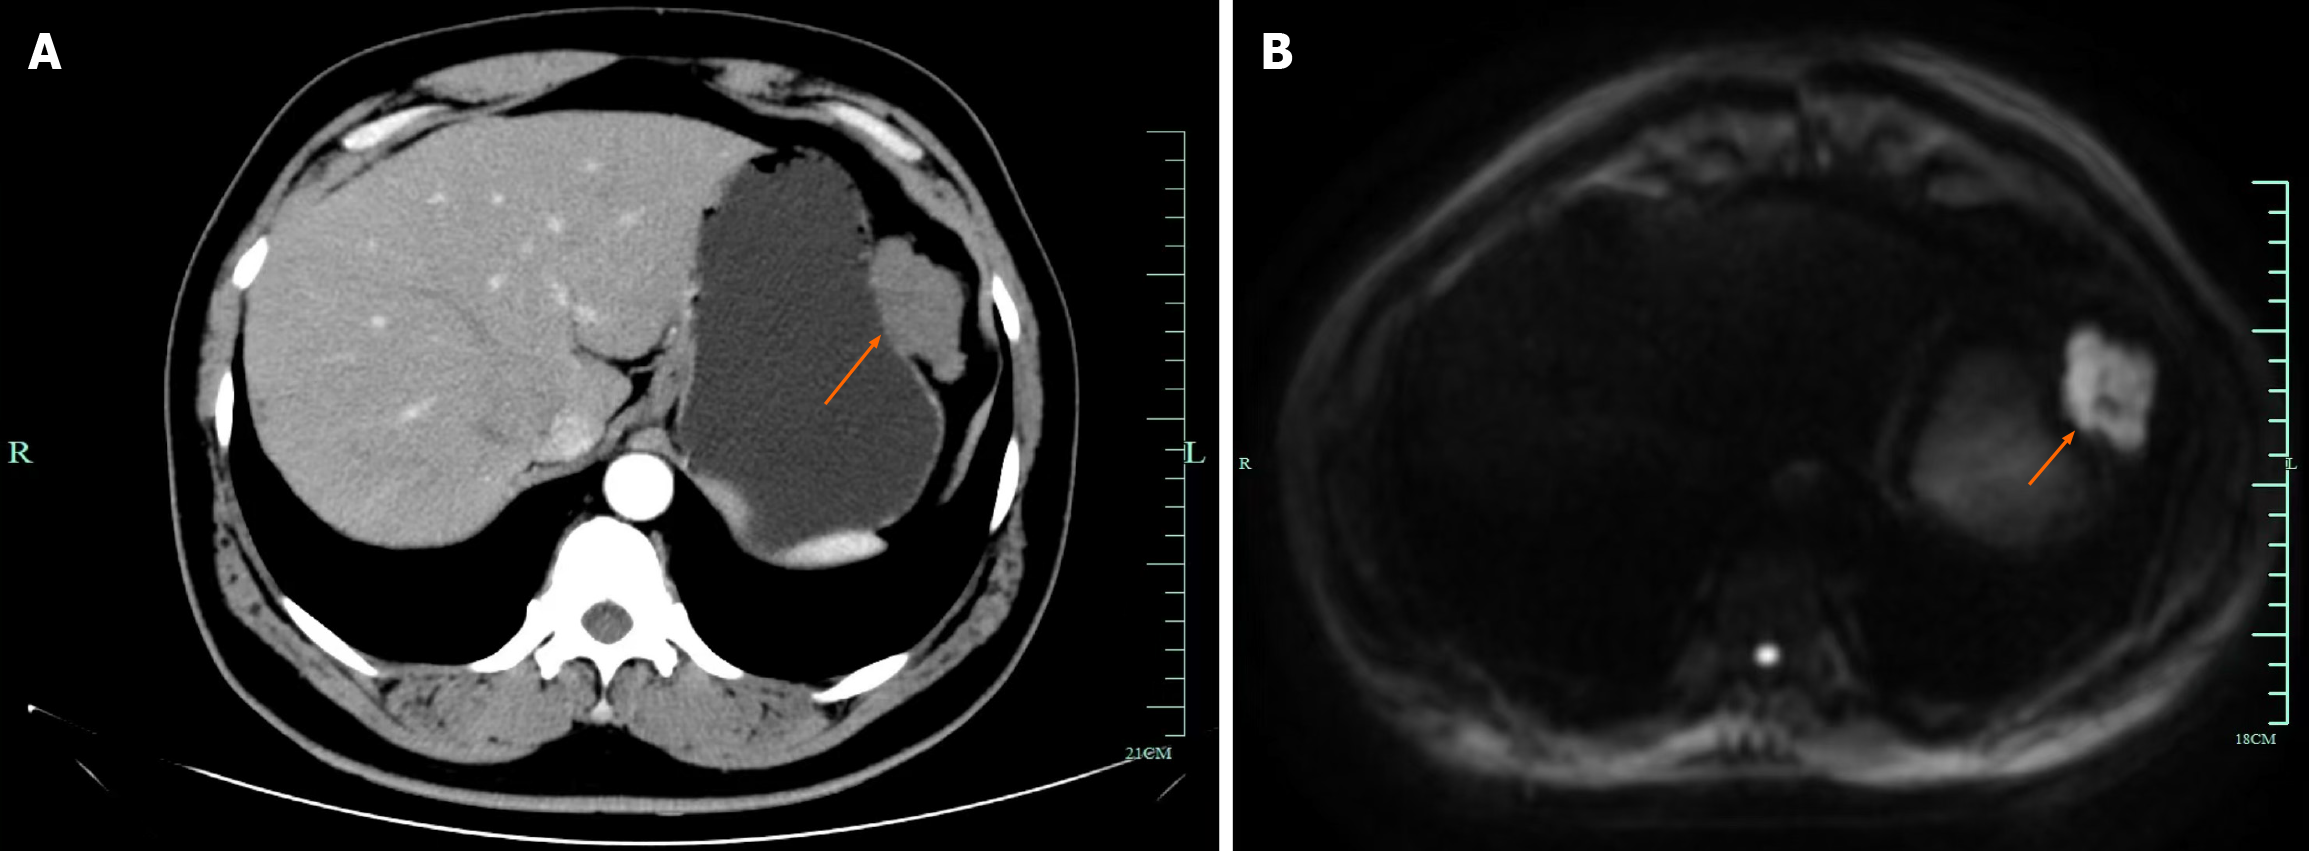

Case 2: CT scan revealed a solid mass lesion in the small intestine within the abdominal cavity (Figure 2).